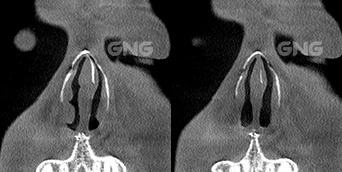

⭐ 비중격만곡증, 비밸브 협착 20대 남자 환자분의 코막힘 수술 케이스왼쪽 코막힘을 심하게 앓고 계셔서 내원하셨습니다.왼쪽 상방 부분에는 비밸브가 위치하고 있는데요.비중격과 왼쪽 측벽 사이의 공간이아예 없는 완전 협착 상태였습니다.비밸브 교정술을 통해가운데로 기둥을 옮겨 주어비밸브 쪽의 공간과 양쪽 비강이비슷해지게 맞춰주었습니다. 뒤쪽에서 본 CT에서도비중격 뼈가 . . .